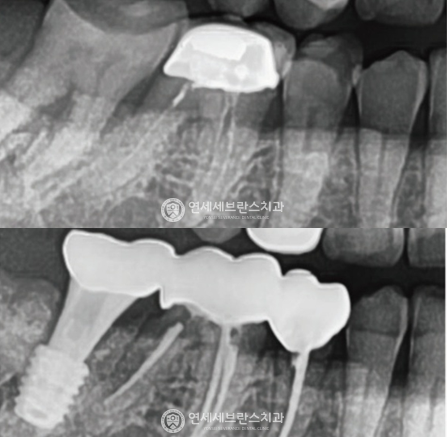

03

전악 임플란트

치아가 하나도 없거나 심각한 구강질환을 앓고 있어도

전악 보철을 제작, 임플란트를 치조골에 식립해

기능적, 심미적으로 자연치아와 가장 유사한 수준으로 재현이 가능합니다.